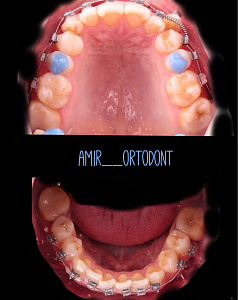

Гегиров Амир Артурович (@amir__ortodont)

Врач-ортодонт

#repost от @amir__ortodont

Была проведена полная фиксация брекетов на обе челюсти, установлены дуги и дополнительные элементы для запуска контролируемого перемещения зубов. Уже с первых месяцев лечения начинается работа над выравниванием зубных рядов, подготовкой места для правильного положения клыков и коррекцией прикуса.

В данном случае наблюдается выраженный дефицит места для клыков, поэтому лечение будет проходить поэтапно и с использованием дополнительной опоры. Каждый элемент системы работает на прогнозируемый и максимально эффективный результат.

Была проведена полная фиксация брекетов на обе челюсти, установлены дуги и дополнительные элементы для запуска контролируемого перемещения зубов. Уже с первых месяцев лечения начинается работа над выравниванием зубных рядов, подготовкой места для правильного положения клыков и коррекцией прикуса.

В данном случае наблюдается выраженный дефицит места для клыков, поэтому лечение будет проходить поэтапно и с использованием дополнительной опоры. Каждый элемент системы работает на прогнозируемый и максимально эффективный результат.